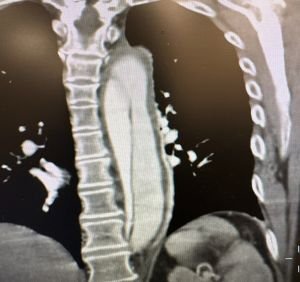

Severe pulmonary edema in a near-SUDEP patient with stereotypical troponin elevations and increased white blood cell counts.

Patients that go into cardiac arrest after a seizure and are successfully resuscitated for at least one hour are said to have experienced a

“near SUDEP”

event. I had such a patient in 2023. She had suffered intermittent epileptic seizures most of her life but never pursued medical care. Thus, she would have met

“probable”

SUDEP criteria had she not been resuscitated. The severity of her pulmonary edema and its correlation with transiently increased white blood cell counts suggest that her seizures triggered a surge of systemic catecholamines

that likely precipitated her sudden and unexpected demise.